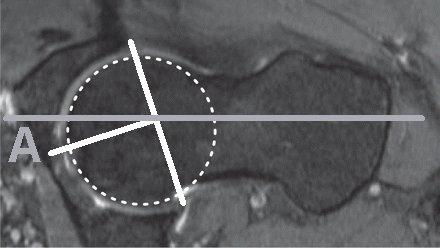

The range of movement before impingement is estimated from sectional images of the hip. A number of parameters have been measured, some completely different measurements have given the same Greek letter! Even reduced to two dimensions there are several parameters to consider:

Notes Clin Orthop Relat Res. 2012 Dec;470(12):3355-60. doi: 10.1007/s11999-012-2477-2. The acetabular wall index for assessing anteroposterior femoral head coverage in symptomatic patients. Siebenrock KA, Kistler L, Schwab JM, Büchler L, Tannast M Loss of rotation due to femoral neck thickening is quantified as the a angle (internal rotation) [ Do normal radiographs exclude asphericity of the femoral head-neck junction? Dudda M, Albers C, Mamisch TC, Werlen S, and Beck M. Clin Orthop Relat R, 2009, 467 (3):651–659. ] and ß angle (external rotation) [ Three-dimensional computed tomography of the hip in the assessment of femoroacetabular impingement. Beaulé PE, Zaragoza E, Motamedi K, Copelan N, and Dorey FJ. J Orthop Res, 2005, 23(6):1286–1292. ]. Available rotation after to acetabular pincer lesions is quantified as over coverage using the lateral centre edge angle, anterior centre edge angle. The combined loss of rotation due to femoral neck thickening and acetabular rim extension/reorientation is